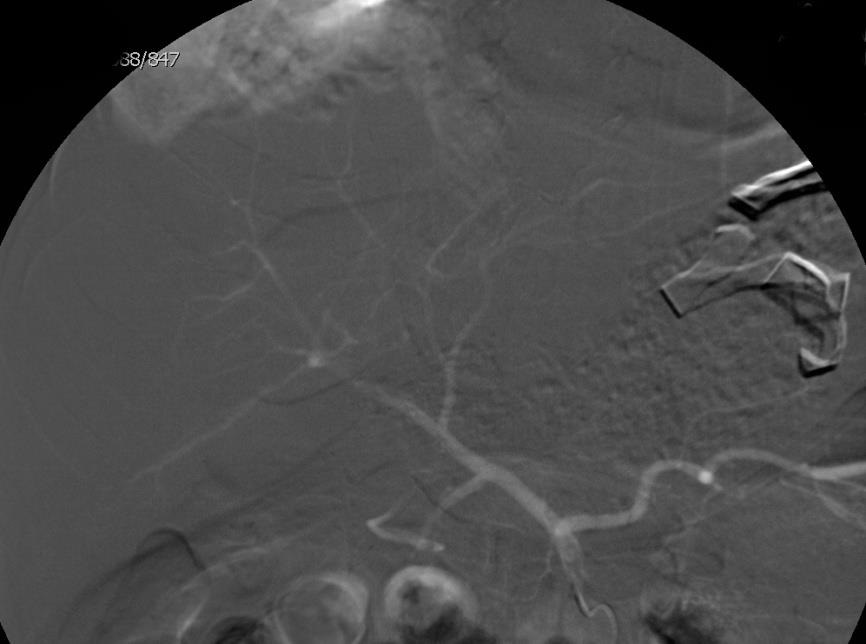

选择性肝动脉造影 |

未发现明确造影剂外溢等出血表现 |

栓塞左肝外侧叶动脉分支(经验栓塞) |